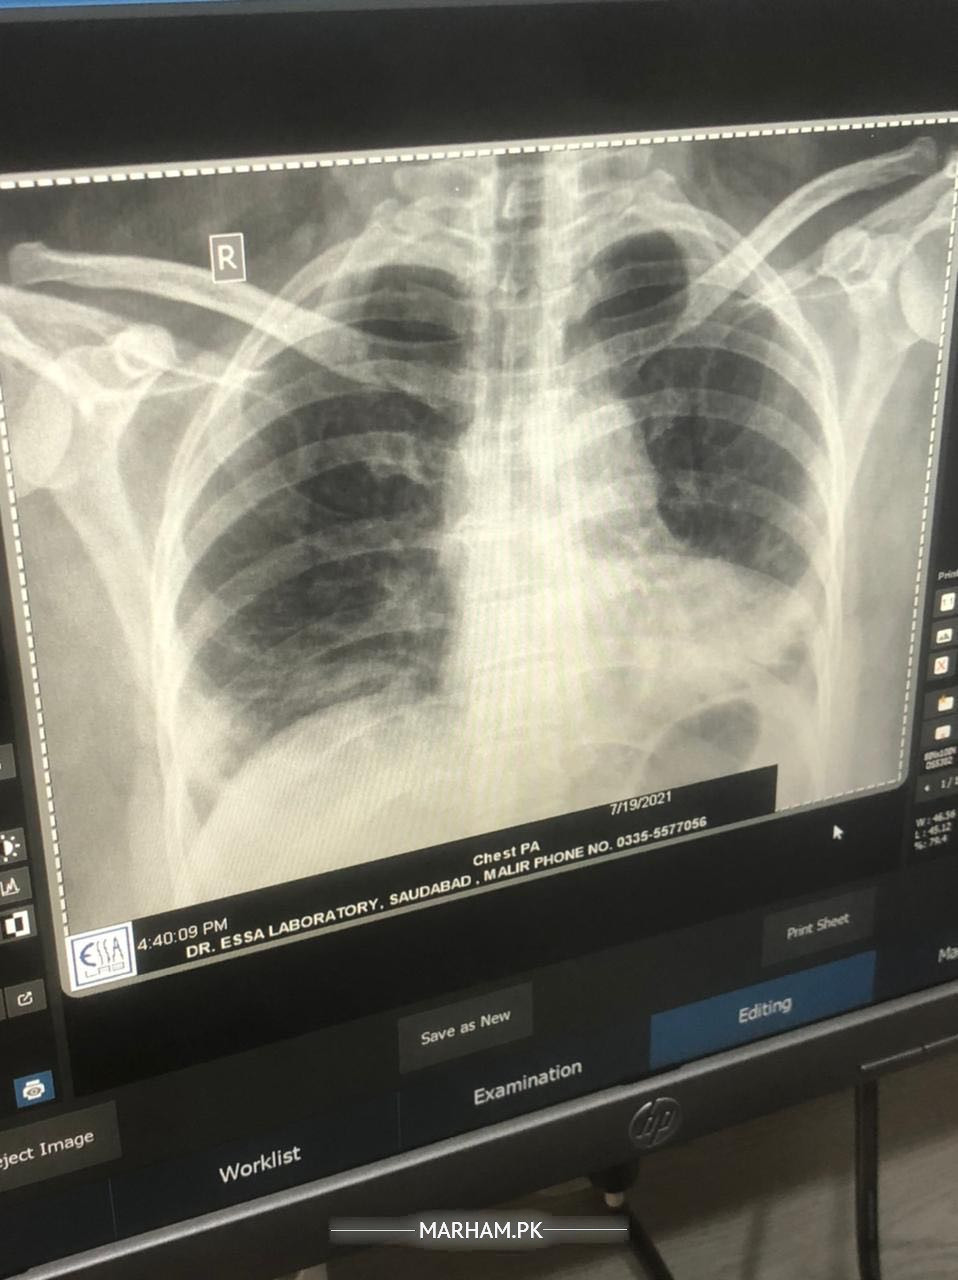

Please examine the x ray and guide is this ok xray is attached. NOTE: She had viral few days back resulting in serious cough and diagnosed with chest infection…. This xray is taken after recovery

comparison with previous x-ray required

yes chest infection